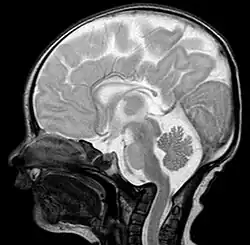

Basilar invagination is invagination (infolding) of the base of the skull that occurs when the top of the C2 vertebra migrates upward. It can cause narrowing of the foramen magnum (the opening in the skull where the spinal cord passes through to the brain). It also may press on the lower brainstem.[1]

Diagnosis

A doctor will base his or her diagnosis on the symptoms the patient has and the results of tests, including:

- An X-ray

- Magnetic resonance imaging (MRI), which usually provides the most information

- Computed tomography (CT) scan [2]